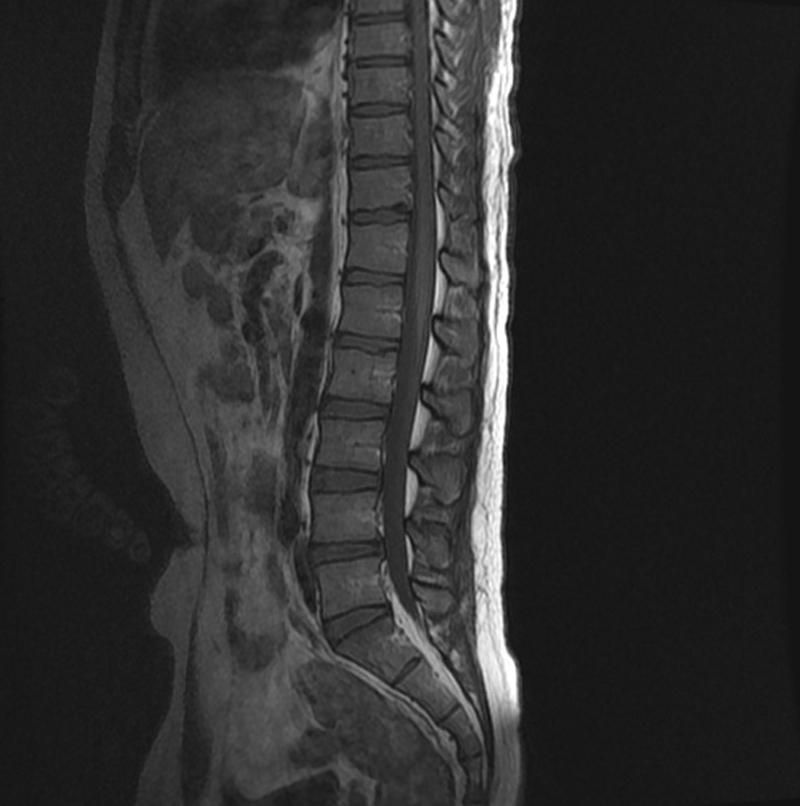

척추 mri 탈수초 여부(사진있음.)

혹시 해당 척추mri에 탈수초 부분이 있나요

등뼈가 아파서 찍었었는데(1달 전) 오늘 갑자기 하체 힘 풀리는 느낌이 나서요 부탁드립니다

MRI 판독지에 탈수초화 소견이 있다면 언급이 있을 것입니다.

T2 혹은 FLAIR 영상에서 척수에 밝은 색으로 보일 것이며

그것이 하나의 image가 아닌 여러 image에서 같은 부위에서

확인이 될 것입니다.